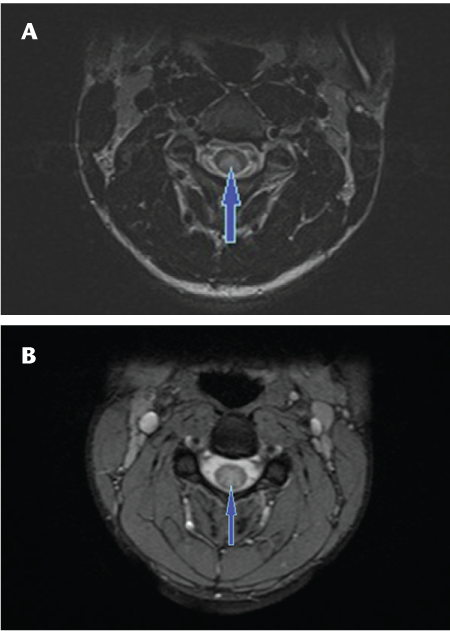

Long-segment linear T2-hyperintense lesions in the spinal cord have been shown to be characteristic of NMO myelopathy.16 17 Additionally, in our experience the typical lesions are symmetrical and centrally located in the cord (Figures 1 and 2). Those seen in MS myelopathies are usually less extensive on cross-sectional imaging and are typically asymmetrical and located at or near the periphery of the cord (Figure 3).

Axial T2 fast spin echo (A) and axial T2 gradient (B) images of the cervical cord showing central T2 hyperintensity (arrows) in neuromyelitis optica involving central portions of the spinal cord with signal changes involving more than 50% of the cross-sectional area